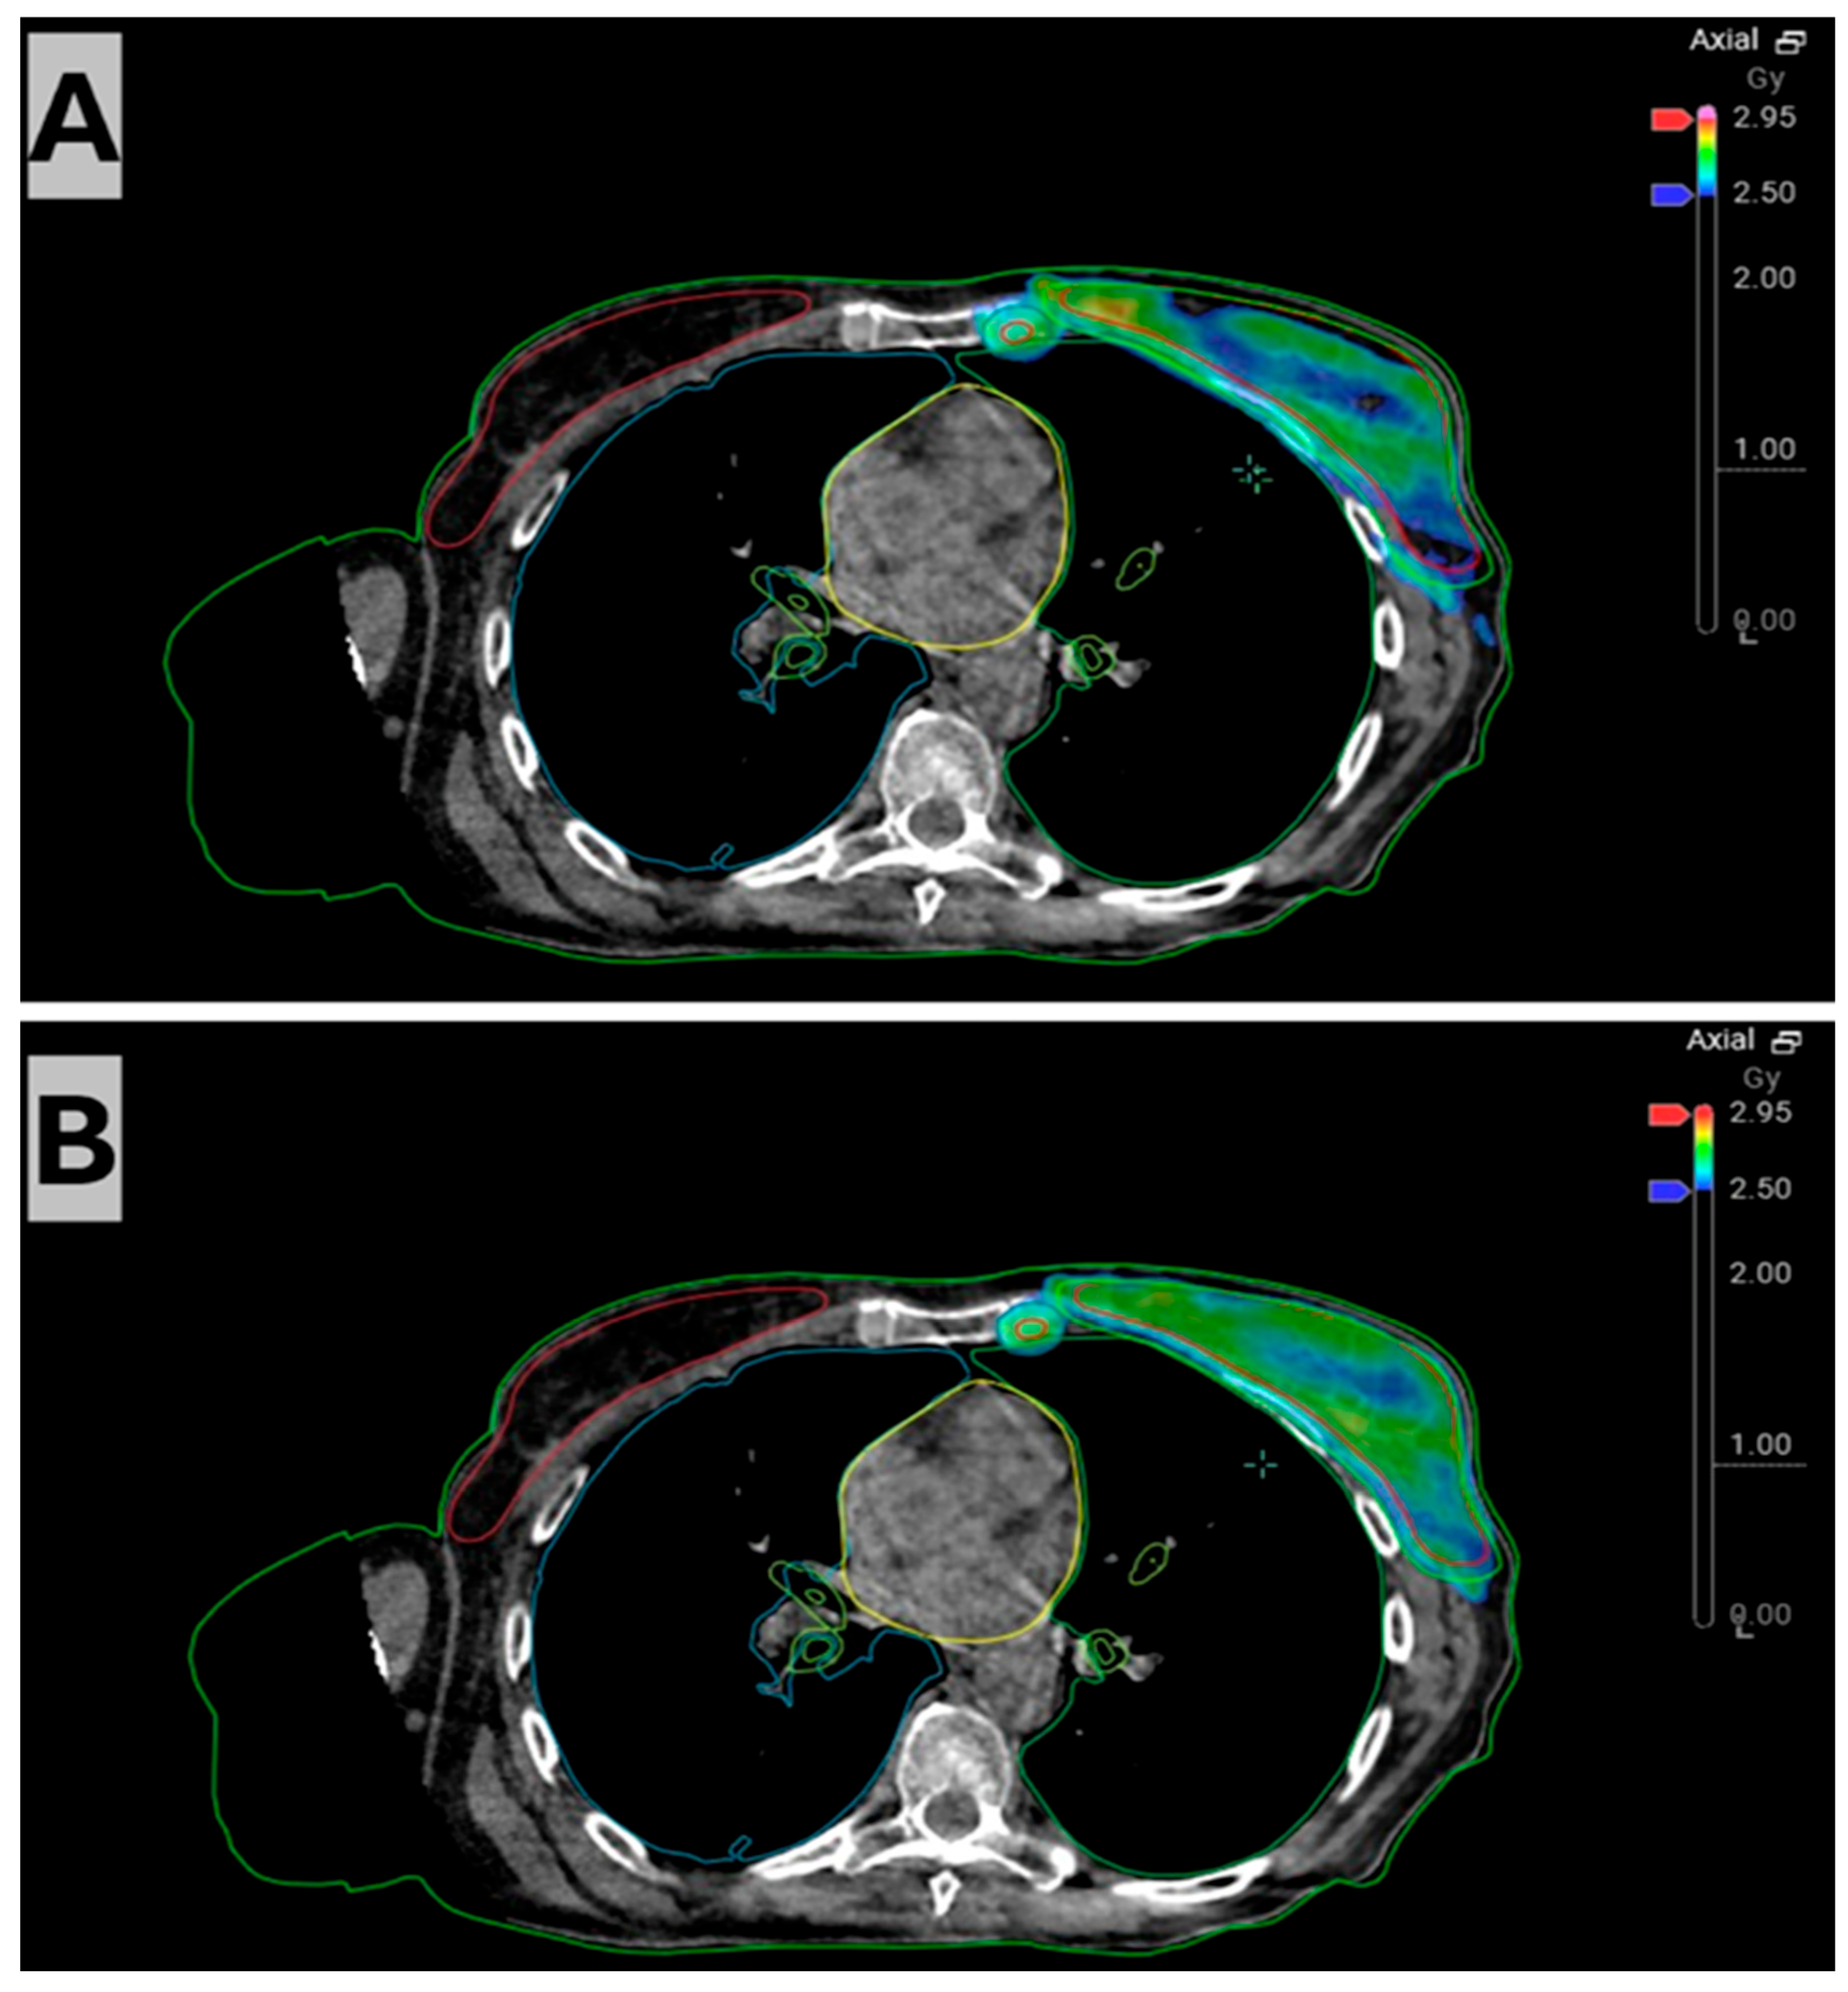

2. Case Description